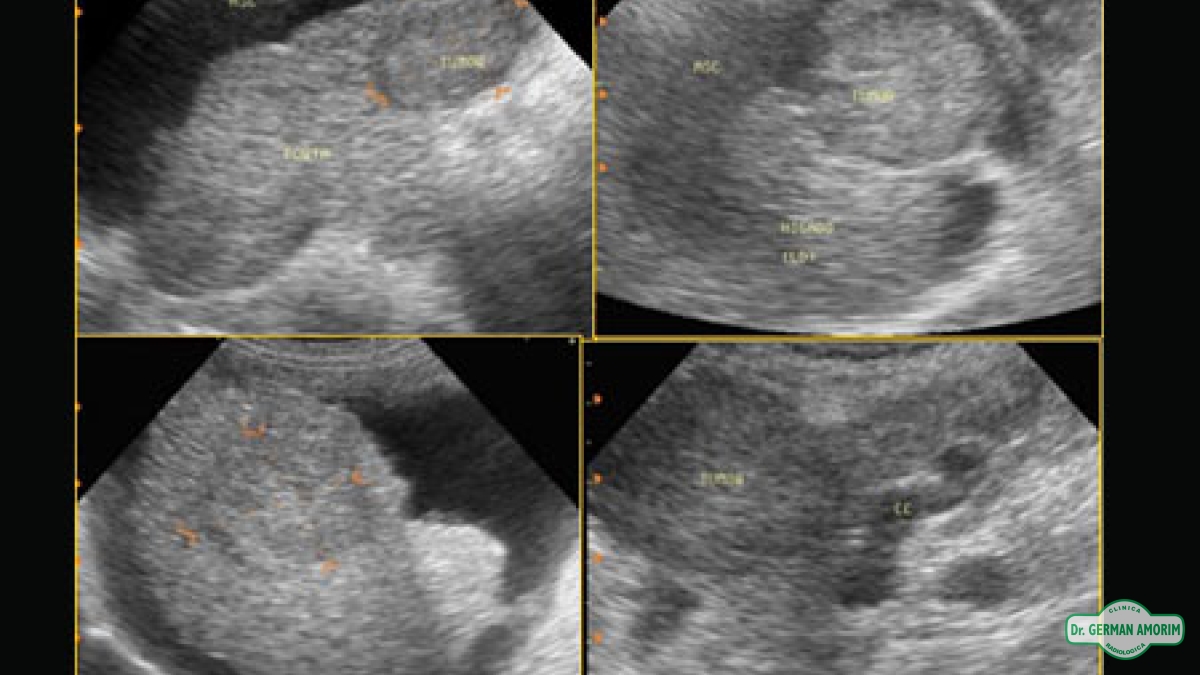

Ecografía de Punciones Hepáticas

La biopsia percutánea es un procedimiento fundamental para el estudio de las enfermedades hepáticas.

Bien sea para su diagnóstico, para la respuesta al tratamiento; para la evacuación de derrames, abscesos y obtención de material para posterior estudio citológico.

Esta técnica se utiliza mucho a partir de la mejora de las imágenes obtenidas con ecógrafos de última generación. Reduciendo así gran parte de las complicaciones observadas cuando se realizaban ciegas.

Con la guía ecográfica es posible controlar en tiempo real el avance de la aguja.